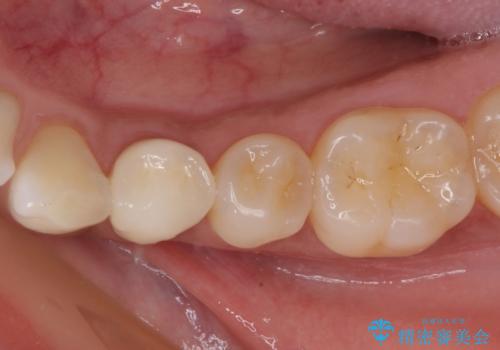

根管治療後は症状を確認し、速やかにオールセラミッククラウンにて補綴治療を行うこととしました。

4ヶ月後のレントゲンでは、病変の消退が認められました。